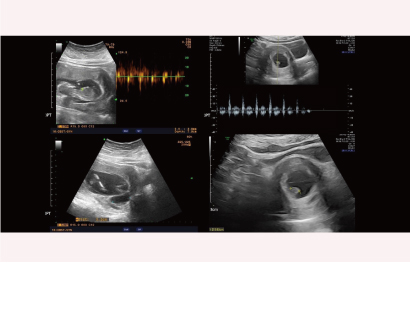

MIRA找出妳的植入時程 2023-12-28

婚後懷孕未果 著床時間異於常人

夫妻婚後未孕且AMH值低,利用MIRA檢測子宮內膜狀態,發現著床時間異於常人,調整後成功生下女寶寶。祝福新手爸媽